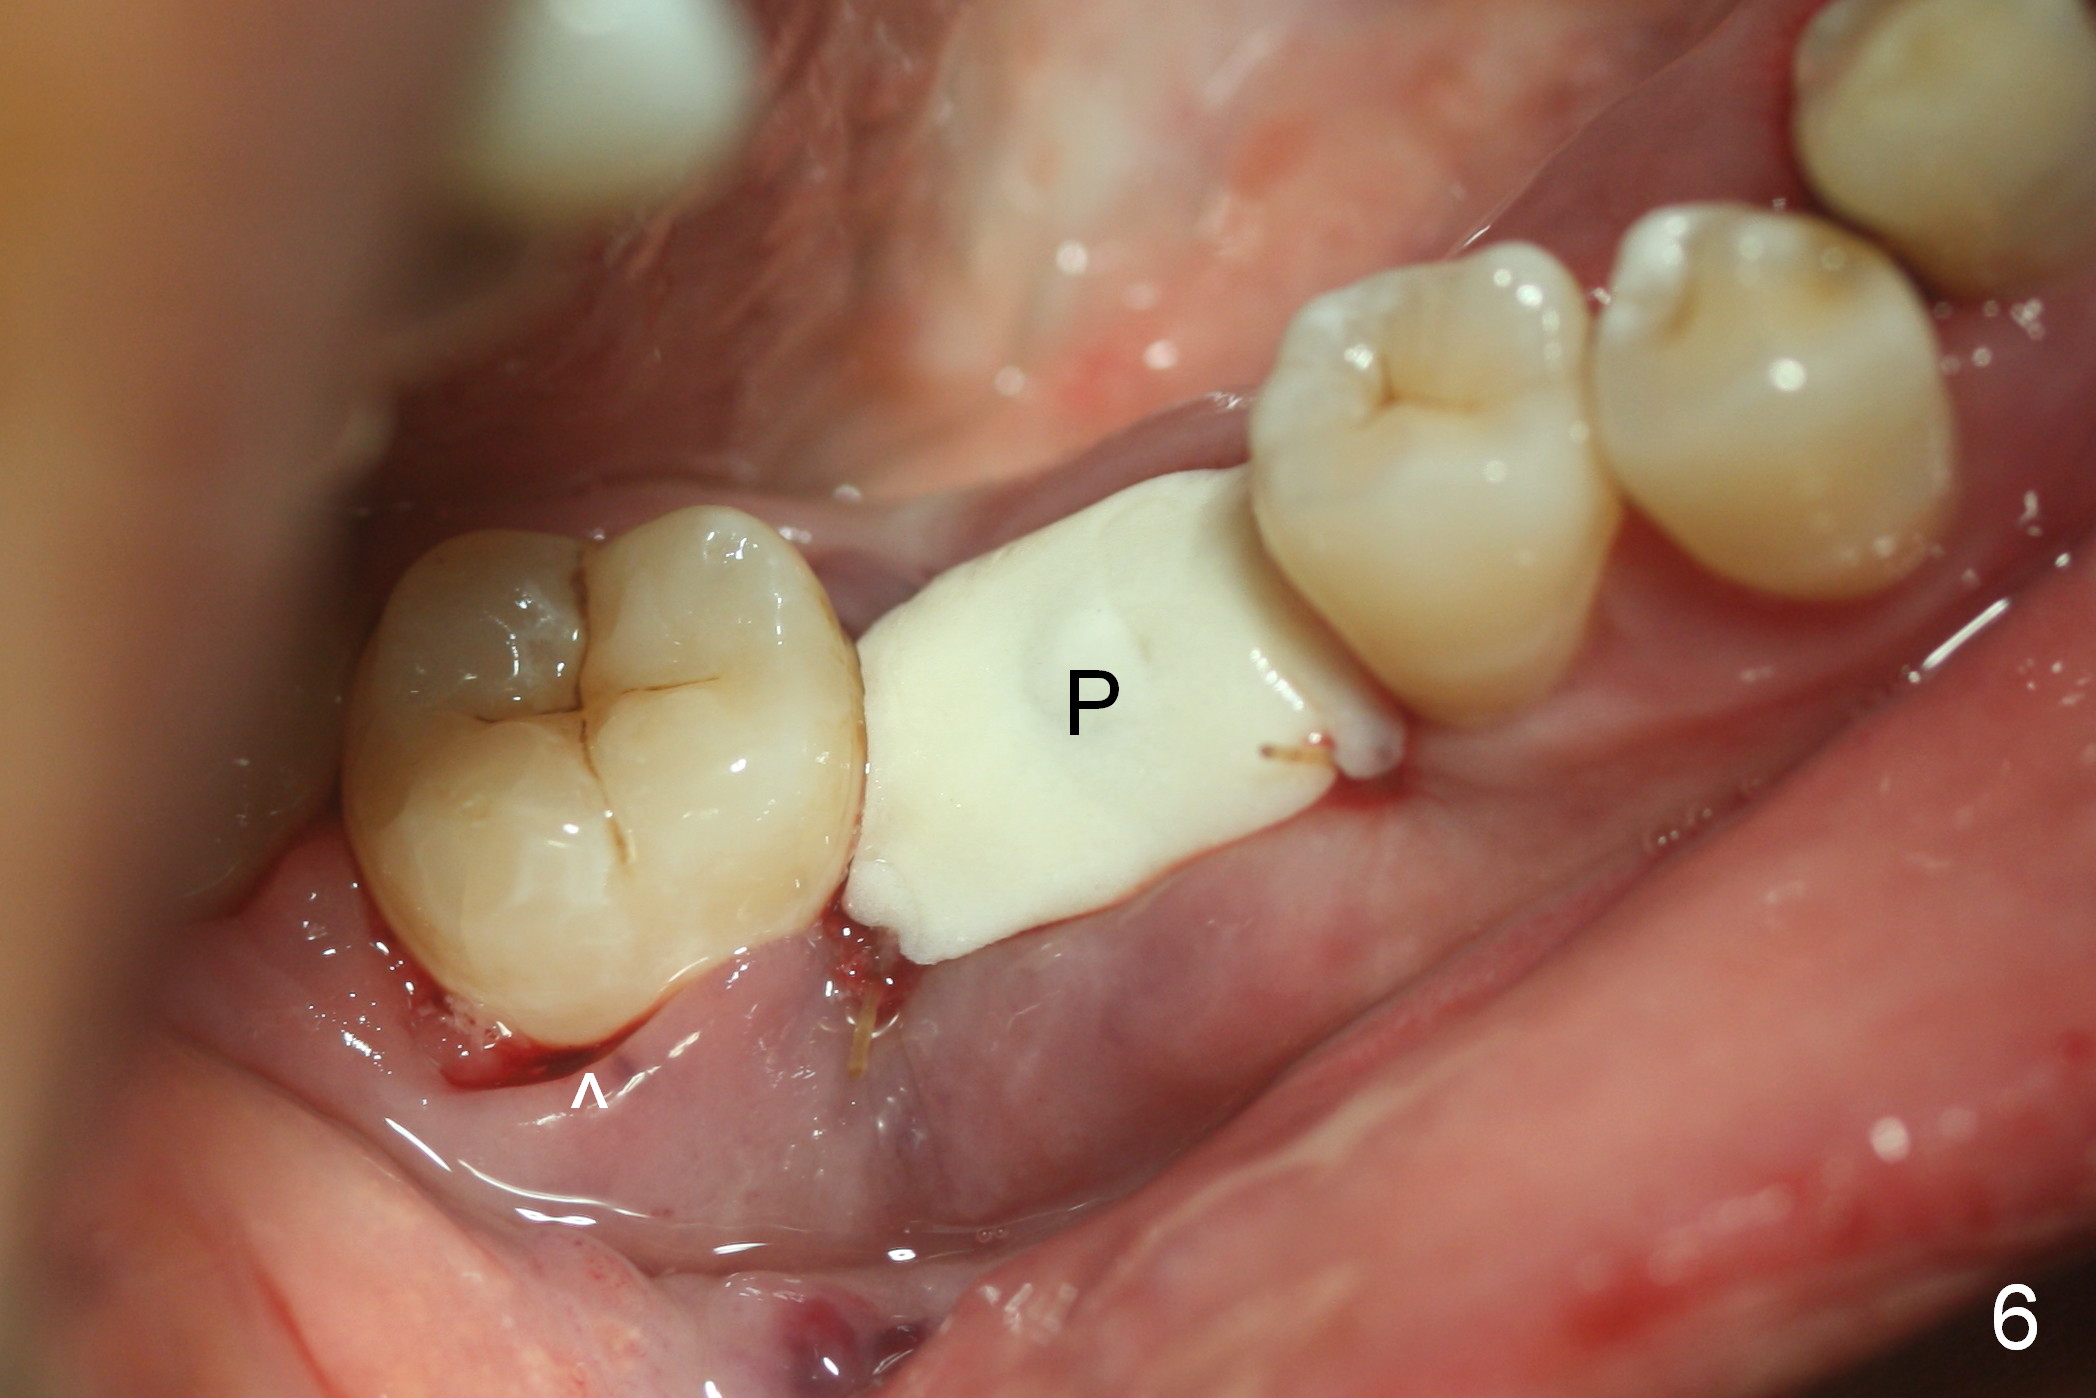

After cleaning the root surface with a surgical curette, a 1.6 mm pilot drill is used to start osteotomy (O) between the mesial (M) and distal (D) roots, followed by a marking bur and 3.8 mm Magic drill 13 mm deep (Fig.1,2). Following root removal, the 3.8 mm drill is reused for 11 mm (Fig.3). After deepening the osteotomy for another 2 mm, a 4.5x13 mm implant is placed with insertion torque of 50 Ncm, followed by allograft (*, .5-2 mm) and a 5x4(2) mm abutment (Fig.4,5). An immediate provisional is fabricated to close the socket (Fig.6 P (lock in)). The detached buccal gingiva (Fig.6 *) is kept in place by applying periodontal dressing (Fig.7 *). Red dashed lines in Fig.1, 3, 5 represents the superior border of the Inferior Alveolar Canal and Mental Foramen.